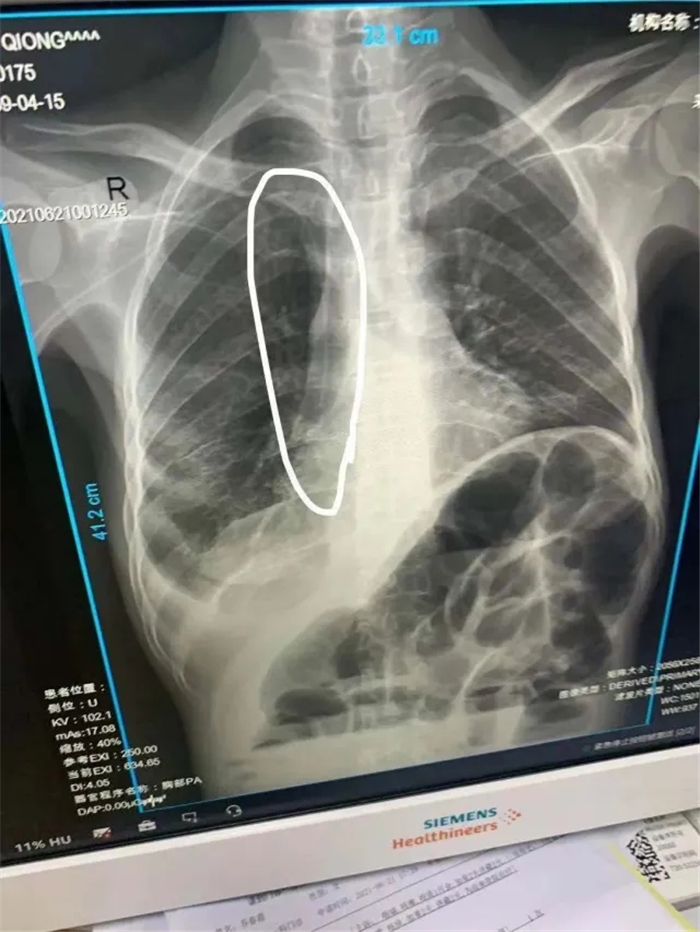

考虑到该患者左侧贵要静脉堵塞,因此术中选取右侧贵要静脉上段为最佳穿刺静脉,沿静脉走行达上腔静脉,并通过拍片确定导管尖端位于上腔静,固定导管,显示导管无异常,PICC尖端位置较好,置管术顺利完成。